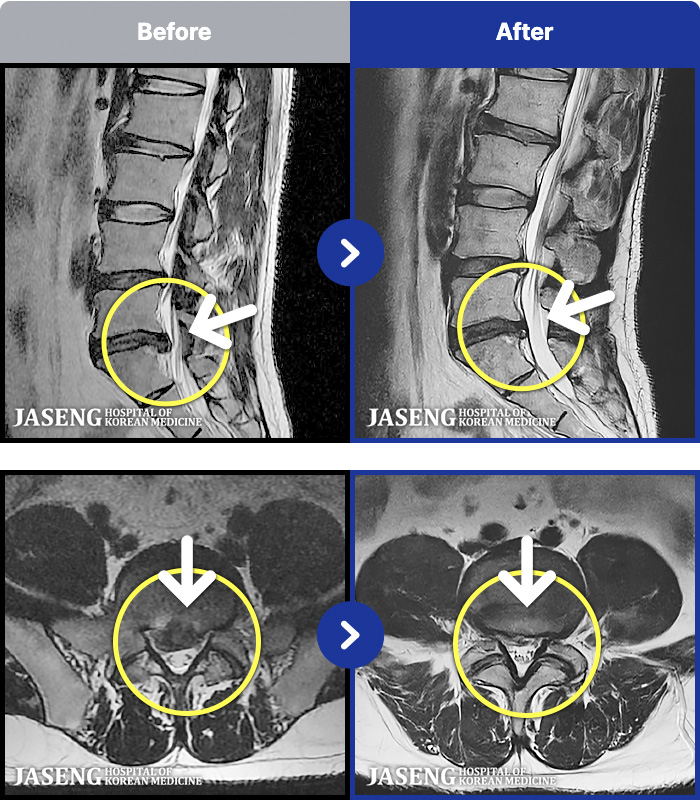

54 MRI ũ ʸ Ȯϼ.